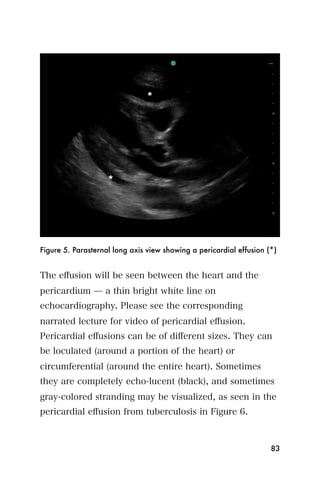

Figure 5. Parasternal long axis view showing a pericardial effusion (*)

The effusion will be seen between the heart and the

pericardium ̶ a thin bright white line on

echocardiography. Please see the corresponding

narrated lecture for video of pericardial effusion.

Pericardial effusions can be of different sizes. They can

be loculated (around a portion of the heart) or

circumferential (around the entire heart). Sometimes

they are completely echo-lucent (black), and sometimes

gray-colored stranding may be visualized, as seen in the

pericardial effusion from tuberculosis in Figure 6.